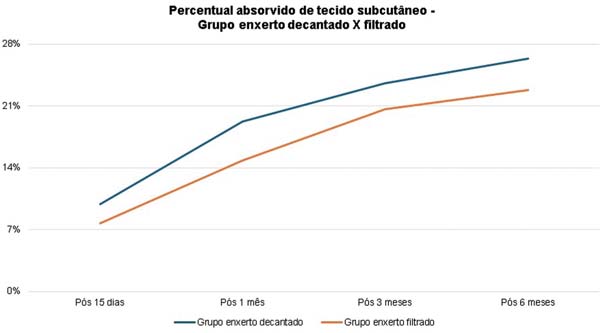

No grupo enxerto decantado, a reducãomédia, comparando-se a espessura inicial apos lipoenxertia, foi de 9,90% no 15° dia, 19,27% no 1° mes, 23,59% no 3° mes e 26,36% no 6° mes. No grupo enxerto filtrado, a reducao media, comparando-se a espessura inicial apos lipoenxertia, foi de 7,74% no 15° dia, 14,85% no 1° mes, 20,67% no 3° mes e 22,80% no 6° mes. ►Fig. 6. A evolução ao ultrassom da espessura do tecido subcutâneo antes e depois da lipoenxertia pode ser vista nas ►Figs. 7-8. Os resultados de pré-e pós-operatório de uma paciente de cada um dos grupos estão exibidos nas ►Figs. 9-10.

A comparacao da reducao da espessura subcutanea em 6 meses entre as te cnicas de decantai; a o e filtrai; a o do enxerto na o mostrou diferenc a estatística significativa (p = 0,59).